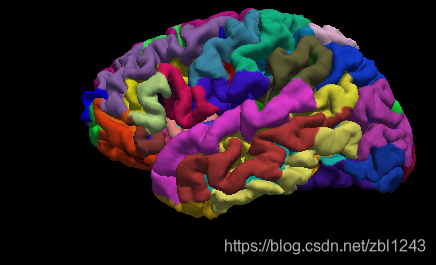

上图不同的分割分到的结果不一样,有的分的细,有的分的粗。还可以利用第三方的库,作为新的分割模板。

还有 .label文件,上图中每一个颜色块都是一个label .

.pial加上文件夹中annot: